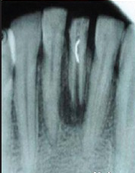

检查可见41牙大面积缺损,牙体变色,髓腔暴露,唇侧可见瘘道口。 X线片发现41牙根尖孔未完全形成,根尖周可见大面积低密度影,根中份可见有一高密度线性影像。仔细询问后发现患者有疼痛时往根管内放置尖锐物体的习惯。

诊断为41牙慢性根尖周脓肿。首先取出41牙根管内尖锐物体,其次完善根管治疗,进行根尖手术,控制根尖周炎症。